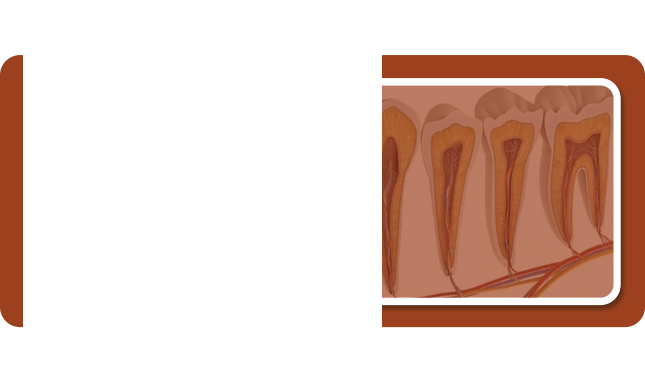

深龋

Level 3 - 疼痛指数:★★★

- 烧钱指数:★★★

- 牙本质深层咬东西感到刺痛,伤及牙神经,此时须进行根管治疗才能拯救你的牙。

- 治疗方法:根管治疗(守住天然牙的最后防线)

- 到院次数:2-3次

- 治疗时间: 1小时/次

牙髓炎

Level4 - 疼痛指数:★★★★★(治疗时会打麻药)

- 烧钱指数:★★★★★

- 若错过根管治疗,齲齿发展到无法拯救的地步,只能进行拔除操作。

- 治疗方法:全瓷牙/种植牙(缺失牙修复的理想选择)

- 到院次数:多次就诊

- 治疗时间:视情况而定